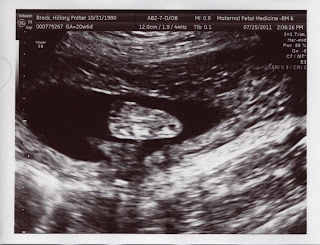

We are happy to report that B.B. checked out well at the anatomy scan today! We have extremely low odds of any birth defects and everything seems to be working as it should--our kid might be more normal than either of us! :) Heartbeat is still up there measuring at 158. Here are some of the latest pics:

Anatomy Scan